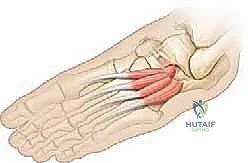

- منع عودة الالتصاق (Interposition): هذه هي الخطوة الحاسمة التي تميز الجراح الخبير. لمنع العظم من النمو والالتصاق مرة أخرى، يجب وضع "حاجز" في الفراغ الذي تم إنشاؤه. يقوم الدكتور هطيف باستخدام جزء من عضلة مجاورة (Extensor Digitorum Brevis) أو قطعة من النسيج الدهني الحر، وتثبيتها بخيوط جراحية أو مثبتات دقيقة داخل الفجوة العظمية.